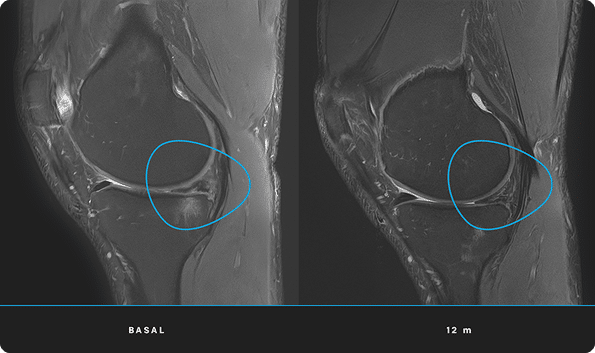

En ITRT hemos demostrado la viabilidad y seguridad de nuestras terapias mediante ensayos clínicos regulados y autorizados por la AEMPS (Agencia Española de Medicamentos y Productos Sanitarios). Una vez superado el ensayo clínico, la AEMPS autoriza el uso del medicamento en pacientes concretos, lo que permite ofrecer tratamientos personalizados con eficacia clínica y capacidad regenerativa demostrada.